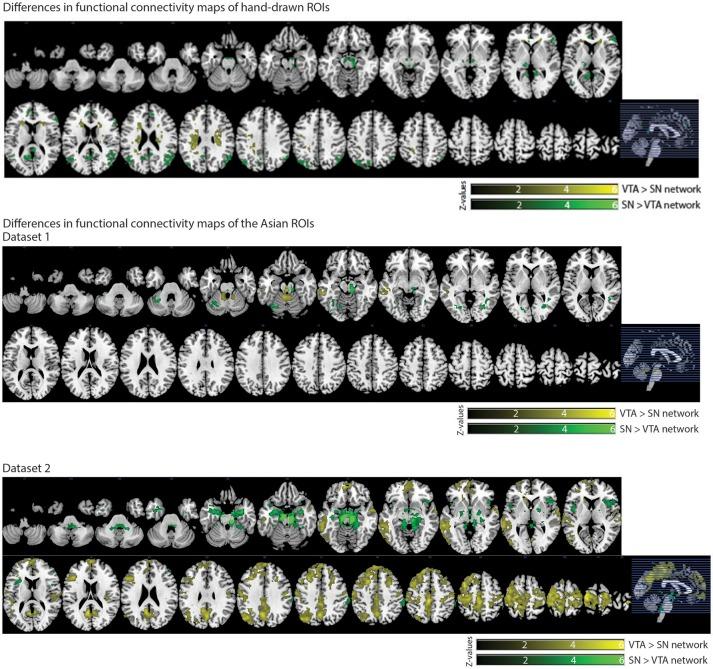

Increasing evidence shows that the midbrain dopaminergic system is involved in various functions. However, details of the role of the midbrain dopaminergic system in these functions are still to be determined in humans. Considering that the ventral tegmental area (VTA) and substantia nigra (SN) in the midbrain are the primary dopamine producers, creating reliable anatomical templates of the VTA and SN through neuroimaging studies would be useful for achieving a detailed understanding of this dopaminergic system. Although VTA and SN anatomical templates have been created, no specific templates exist for the Asian population. Thus, we conducted anatomical and resting-state functional magnetic resonance imaging (rs-fMRI) studies to create VTA and SN templates for the Asian population. First, a neuromelanin-sensitive MRI technique was used to visualize the VTA and SN, and then individual hand-drawn VTA and SN regions of interests (ROIs) were traced on a small sample of neuromelanin-sensitive MRIs (dataset 1). Second, individual hand-drawn VTA and SN ROIs were normalized to create normalized VTA and SN templates for the Asian population. Third, a seed-based functional connectivity analysis was performed on rs-fMRI data using hand-drawn ROIs to calculate neural networks of VTA and SN in dataset 1. Fourth, a seed-based functional connectivity analysis was performed using VTA and SN seeds that were created based on normalized templates from dataset 1. Subsequently, a seed-based functional connectivity analysis was performed using VTA and SN seeds in another, larger sample (dataset 2) to assess whether neural networks of VTA or SN seeds from dataset 1 would be replicated in dataset 2. The Asian VTA template was smaller and located in a more posterior and inferior part of the midbrain compared to the published VTA template, while the Asian SN template, relative to the published SN template, did not differ in size but was located in the more inferior part of the midbrain. The neural networks of the VTA and SN seeds in dataset 1 were replicated in dataset 2. Altogether, our normalized template of the VTA and SN could be used for measuring fMRI activities related to the VTA and SN in the Asian population.

越来越多的证据表明,中脑多巴胺能系统参与多种功能。然而,中脑多巴胺能系统在这些功能中的具体作用细节在人类中仍有待确定。鉴于中脑的腹侧被盖区(VTA)和黑质(SN)是主要的多巴胺产生部位,通过神经影像学研究创建VTA和SN可靠的解剖模板将有助于深入了解这个多巴胺能系统。虽然已经创建了VTA和SN解剖模板,但亚洲人群尚无特定模板。因此,我们进行了解剖学和静息态功能磁共振成像(rs-fMRI)研究,以创建亚洲人群的VTA和SN模板。首先,使用一种对神经黑色素敏感的MRI技术来可视化VTA和SN,然后在一小部分对神经黑色素敏感的MRI(数据集1)上手动绘制VTA和SN的感兴趣区域(ROI)。其次,将手动绘制的个体VTA和SN ROI进行归一化处理,以创建亚洲人群的归一化VTA和SN模板。第三,使用手动绘制的ROI对rs-fMRI数据进行基于种子的功能连接性分析,以计算数据集1中VTA和SN的神经网络。第四,使用基于数据集1的归一化模板创建的VTA和SN种子进行基于种子的功能连接性分析。随后,在另一个更大的样本(数据集2)中使用VTA和SN种子进行基于种子的功能连接性分析,以评估数据集1中VTA或SN种子的神经网络是否能在数据集2中得到复制。与已发表的VTA模板相比,亚洲VTA模板更小,且位于中脑更靠后和靠下的部位,而亚洲SN模板与已发表的SN模板相比,大小没有差异,但位于中脑更靠下的部位。数据集1中VTA和SN种子的神经网络在数据集2中得到了复制。总之,我们的VTA和SN归一化模板可用于测量亚洲人群中与VTA和SN相关的fMRI活动。